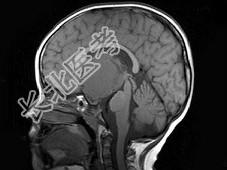

- 单项选择题女,51岁, 视力下降伴左侧面部麻木1个月,MRI检查如图所示, 应考虑为 ( )